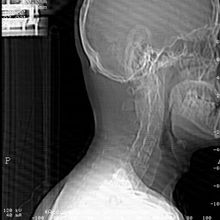

1、或许有人还不清楚的一件事就是强直的诱发因素之一就是受到外界风寒的侵袭,所以要想早日远离强直性脊柱炎就应该注意好自己的保暖工作,尤其是秋冬季节的时候更是这样,很多人在冬季会忽略对自己颈部的保护,时间长了很有可能会引发颈椎强直,那时候就后悔莫及了,所以防范于未然的工作还是要做的。除了颈部的保暖之外,还有哪些比较容易受强直的青睐呢?详情请询问我们的医生,医生咨询QQ:。

3、在坐车的时候很多人都会坐在前面,尤其是比较晕车的人,认为那样眼睛一直向前方看就能舒服些,好受些,可是殊不知这样下去的话当车辆在刹车的瞬间就会很容易造成颈部的损伤,甚至还有一些其他的拉伤,所以乘车的时候较好就是侧坐,对于关节和颈部能够起到一定的保护作用!